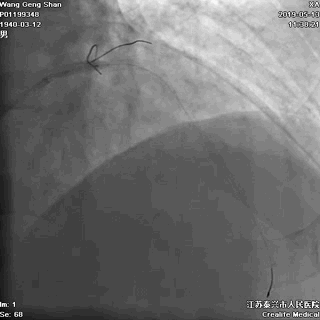

01 导丝进前三叉分支

对角支导丝到位

左冠共计5根导丝